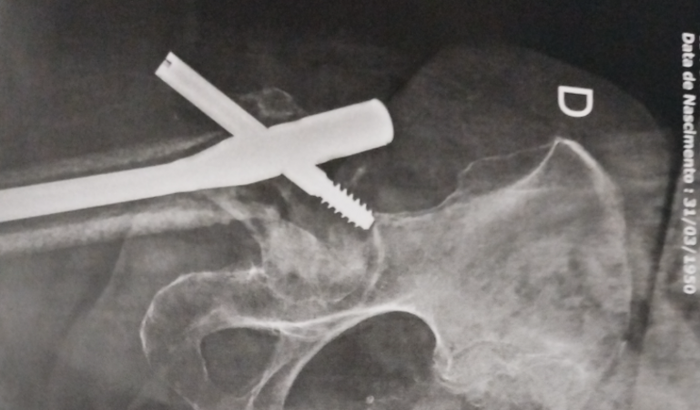

Sou o Lucas, estou desempregado a 9 meses para cuidar da minha mãe que sofreu um acidente doméstico e fraturou o fêmur, ela já passou por 3 cirurgias mas a recuperação está bem lenta, ela ainda não consegue andar, precisa da minha ajuda, criei essa vaquinha pra poder conseguir mil reias e poder pagar as próximas contas da casa. Desde j agradeço muito ajuda de todos.